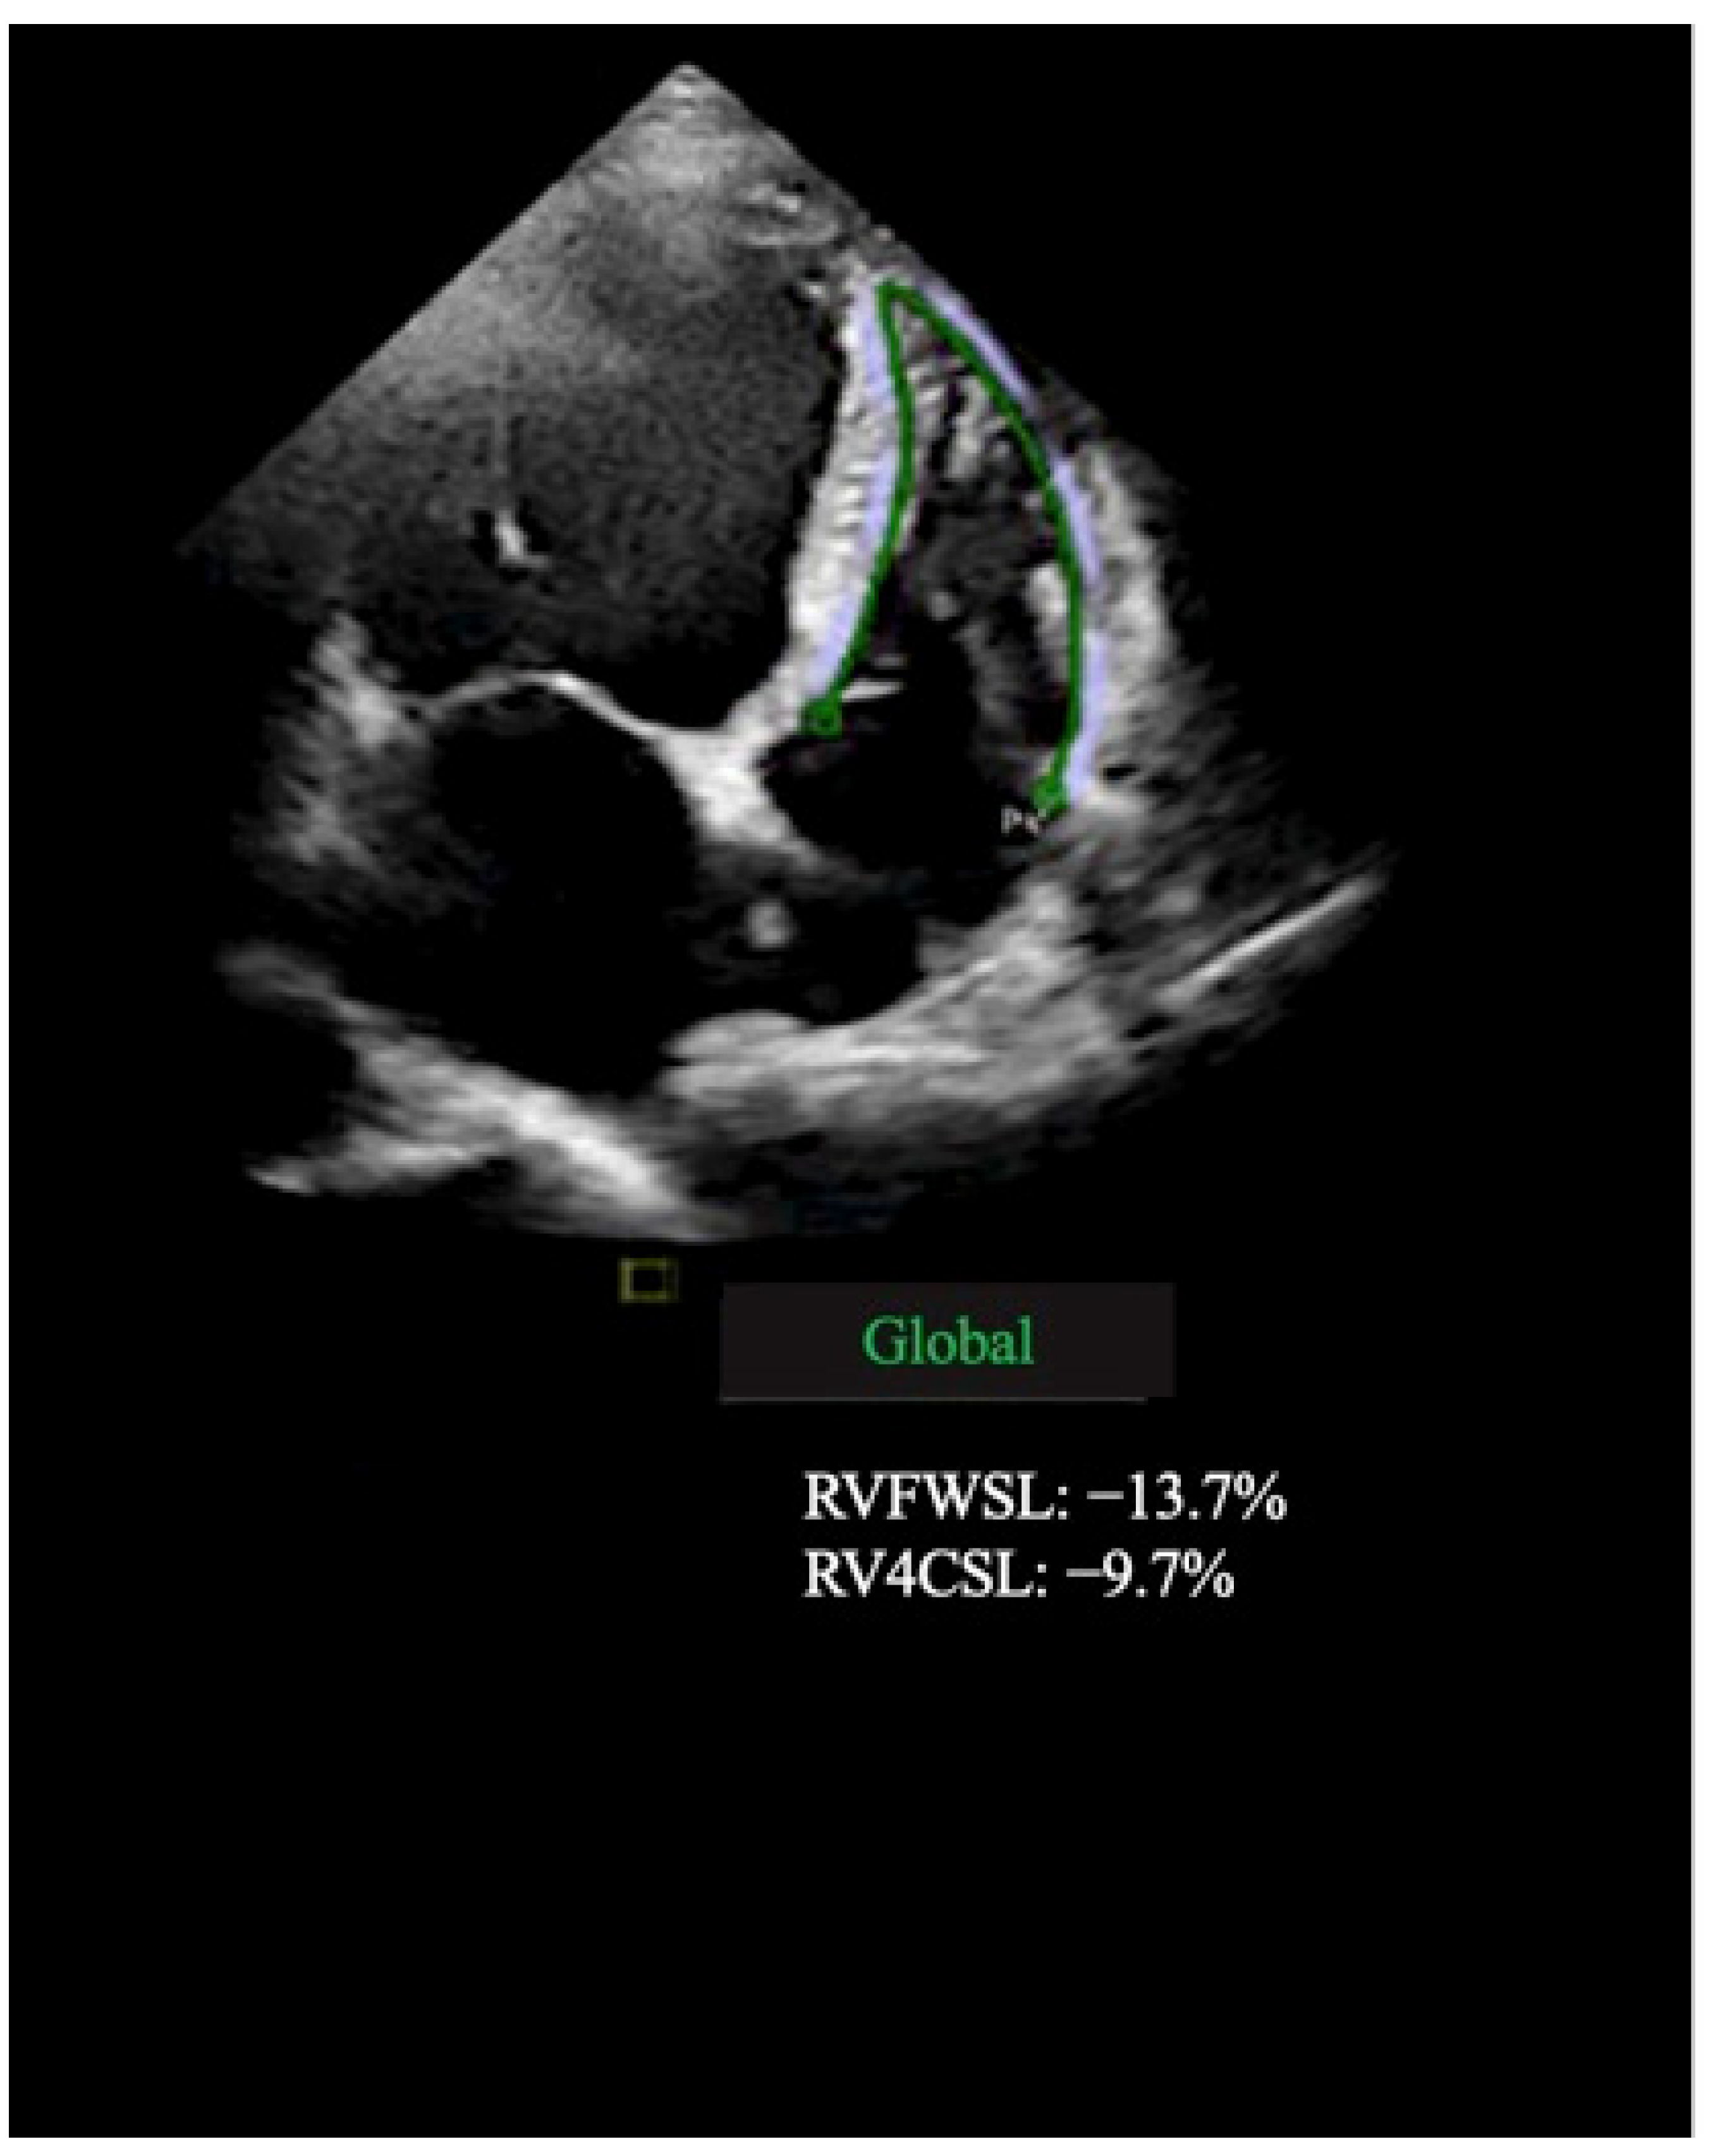

| RV free wall LS, % | −17.3 ± 2.9 | −19.0 ± 2.9 | 0.008 |

| RV GLS, % | −9.5 ± 3.5 | −13.2 ± 4.2 | 0.007 |